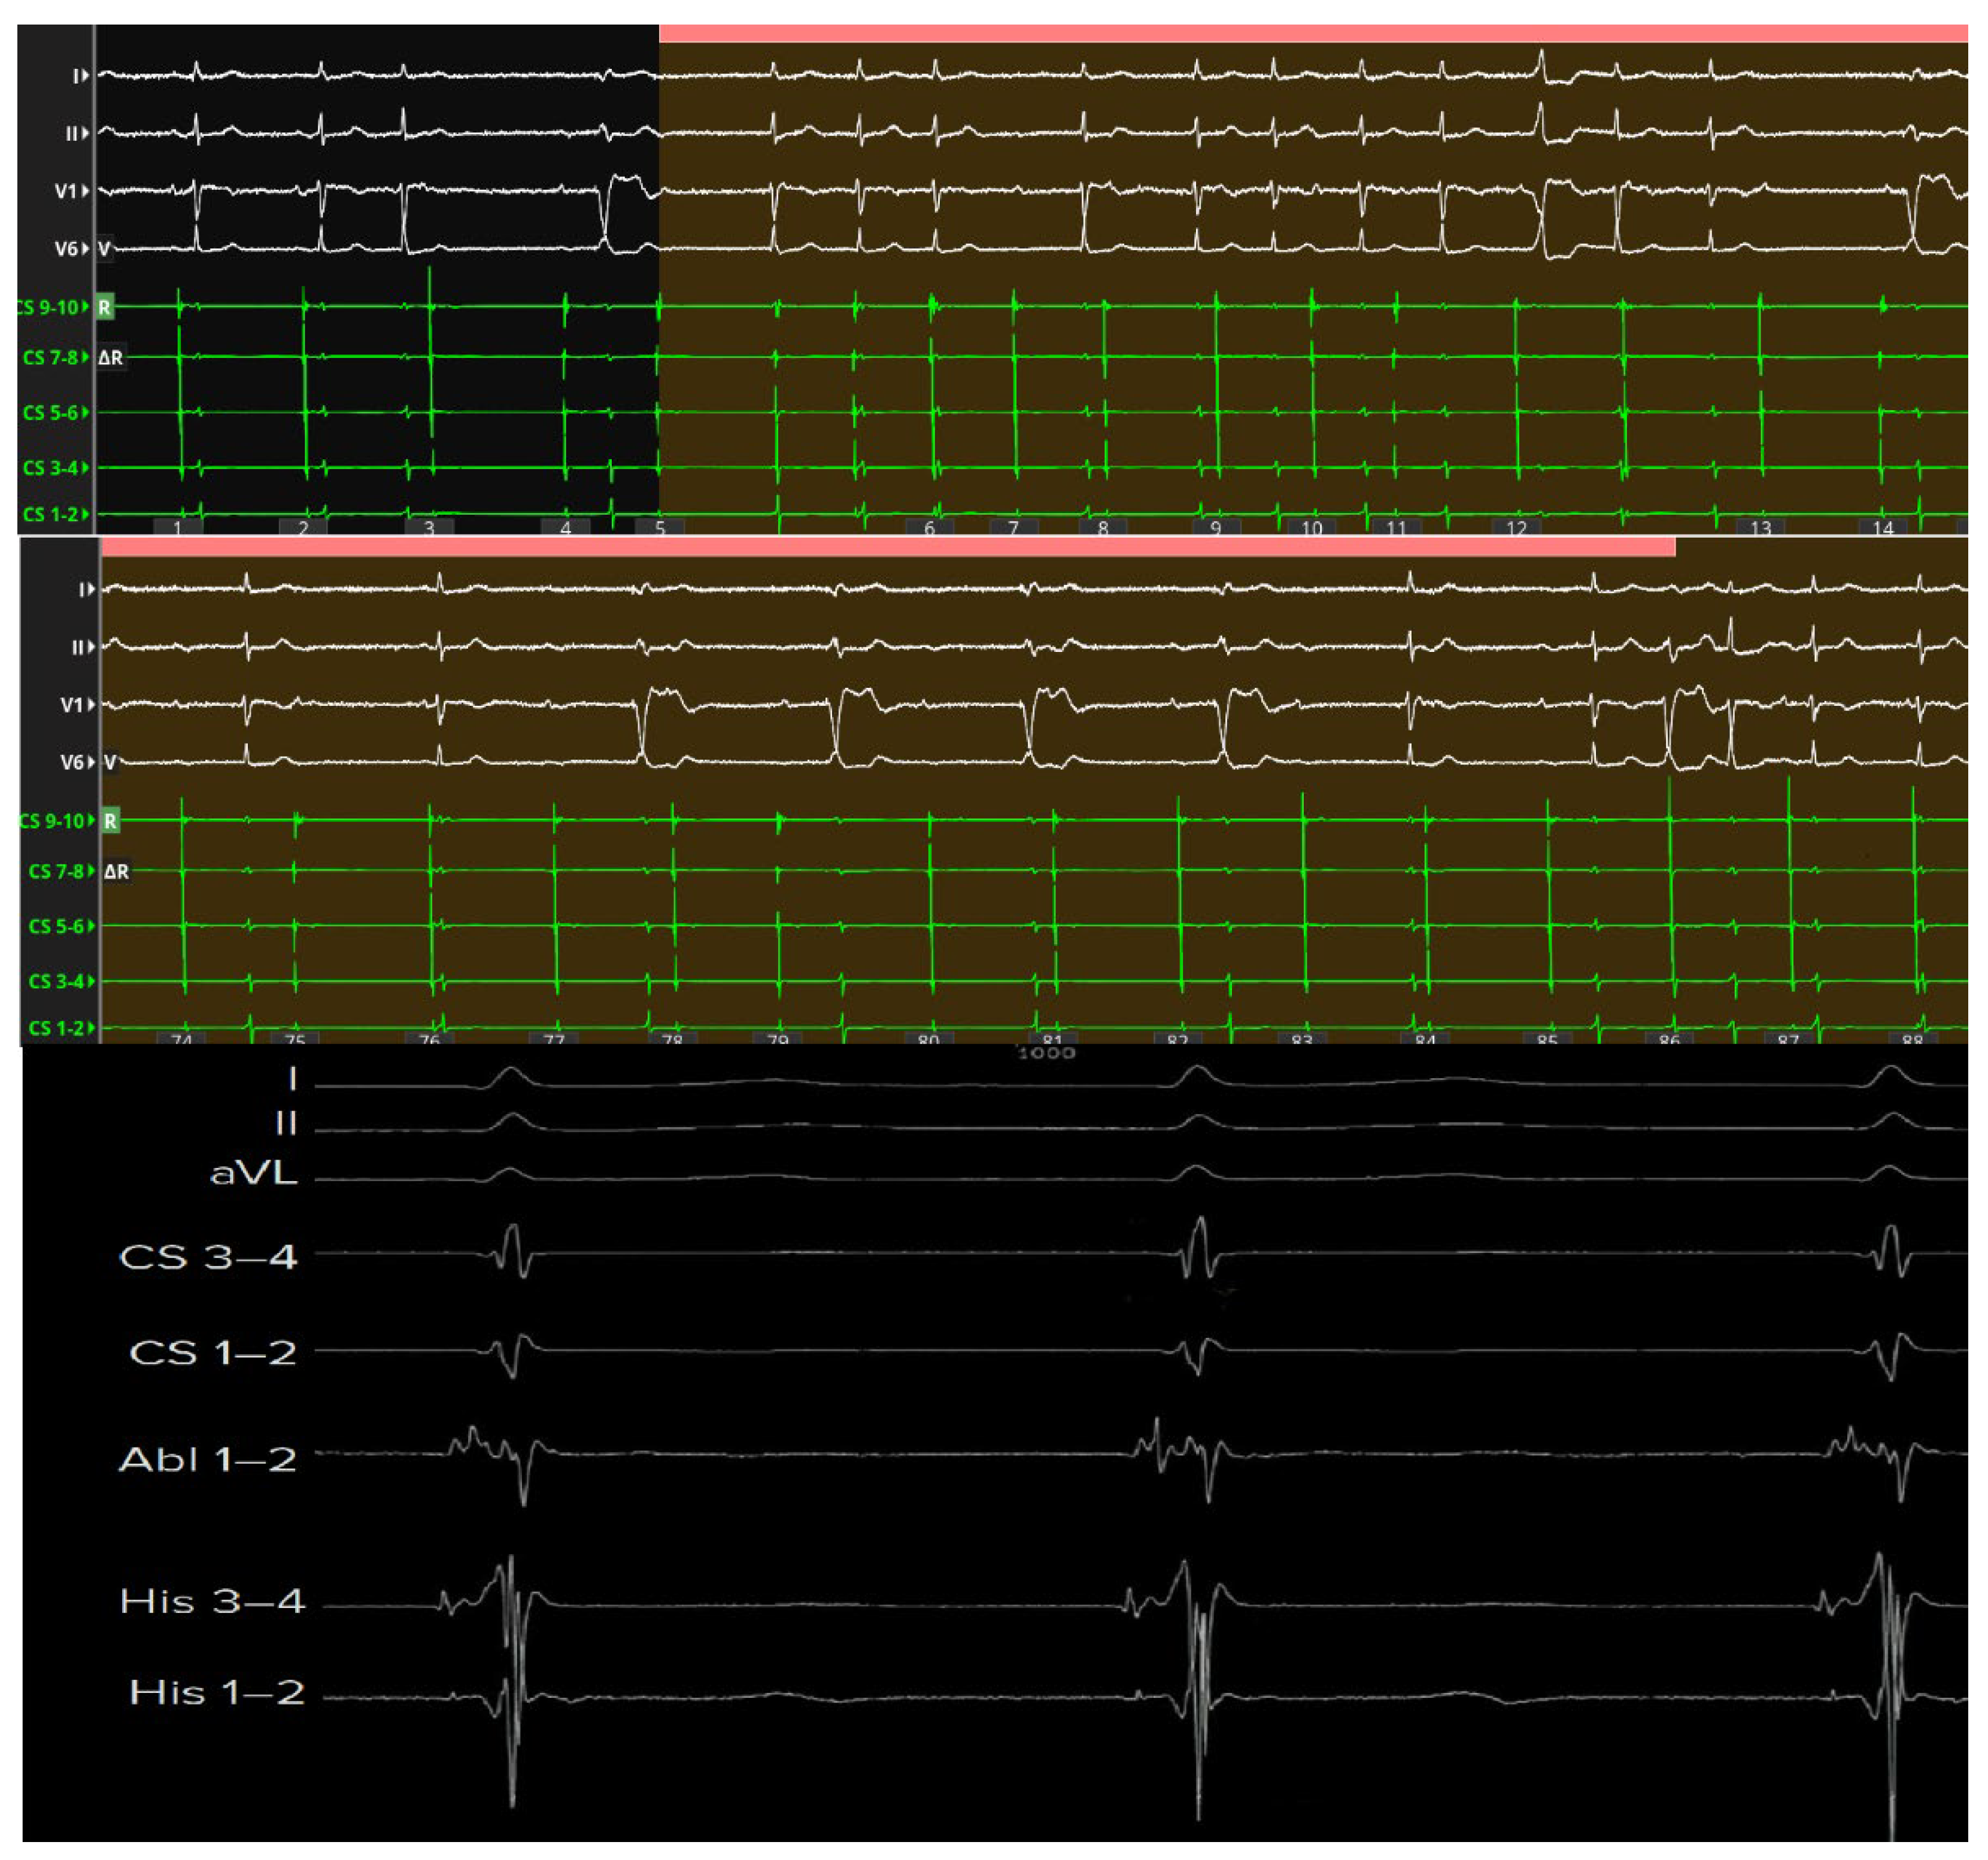

These recordings can also distinguish between the slow potential originating from the SP and the slow potential originating from the compact AV node; in fact, successful ablation has often been achieved at sites where an SP-AV node potential was recorded, without any AV block occurring. Therefore, proceeding in order from the SP region towards the His region, the following can be recorded: (1) the AV node potential together with the SP potential; (2) AV node potential alone; (3) AV node potential hump and high-frequency His potential; (4) His potential alone (Figure 4).

Figure 4. High-definition electroanatomical mapping of the compact AV node before (Panel (A)) and after ablation (Panel (C)). Three-dimensional high-resolution electroanatomical maps (Panels (A,C)) and corresponding intracardiac electrograms (Panels (B,D)) acquired before (Panel (B)) and after (Panel (D)) AV nodal ablation. The compact atrioventricular node (white star) was identified within Koch’s triangle by means of high-density mapping and bipolar filtering (0.1–250 Hz), displaying a characteristic long-duration, low-amplitude, low-frequency “hump” potential (white arrow) confined to the mid- and posteroseptal regions. This nodal potential preceded the onset of the His deflection during sinus rhythm, confirming its origin from the compact AV node. The color-coded activation map illustrates the spatial distribution of nodal and His signals, with ablation lesions (colored spheres) delivered at the anatomical level corresponding to the compact node. Post-ablation recordings demonstrate persistence of a normal His-ventricular interval, indicating preservation of distal conduction through the His–Purkinje system and confirming the selective nature of the nodal lesion.